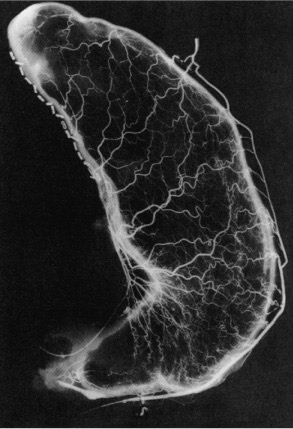

Arteriograma do estômago após preparação para substituição esofágica. A rede arterial intramural é vista suficientemente, mesmo após a ressecção da cárdia e da área gástrica esquerda da pequena curvatura

O estômago é o conduto de escolha pela facilidade na mobilização e o amplo aporte vascula).